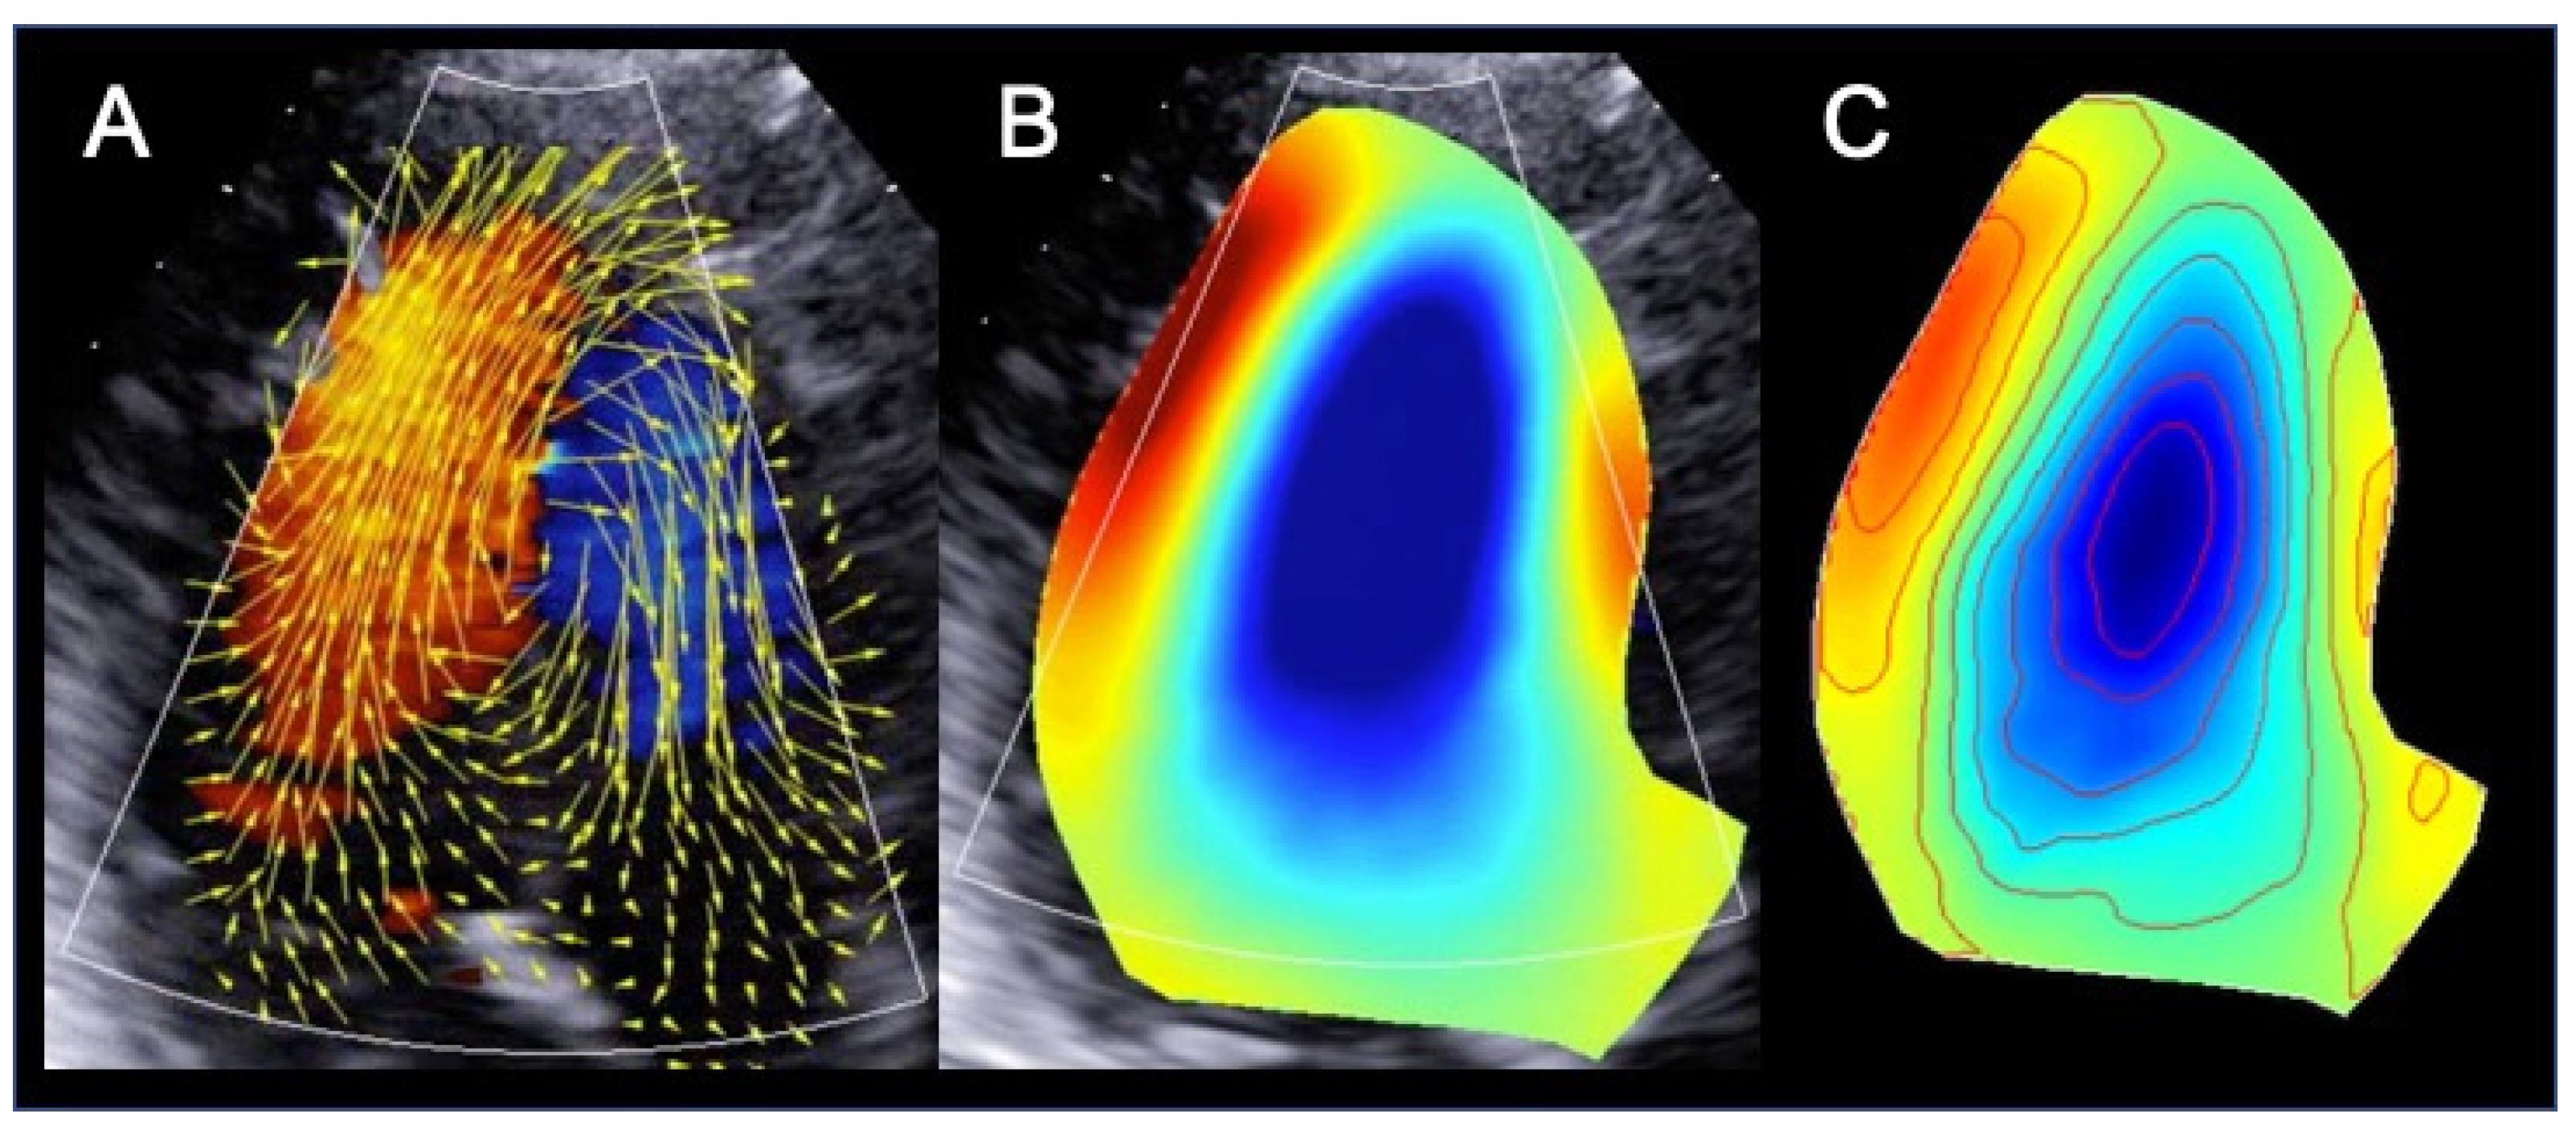

3. Left Ventricular Color Doppler Flow Mapping

3.2. Color Doppler Flow Mapping: The Technique

3.3. Clinical Application of Color Doppler Flow Mapping to Heart Failure